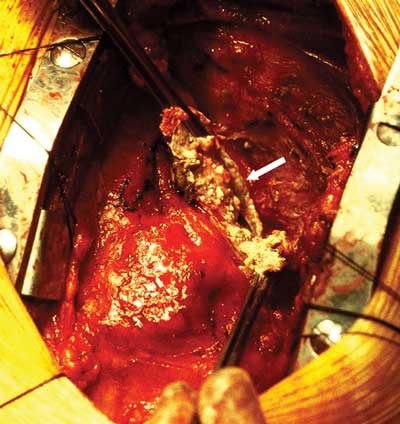

Pericardiectomy with left internal mammary bypass graft to the left anterior descending artery was performed. Severe constrictive pericarditis with a thick (up to 4 mm) layer of calcium plaque was found. Two large cystic masses within a thick calcified shell were present in the posterolateral aspect of the right side of the heart and the left posterior atrioventricular groove. Both contained creamy caseous material, which was drained (Box 3). Histopathological examination was consistent with chronic calcific pericarditis with no granuloma. Microbiological examination and culture did not show any organisms.